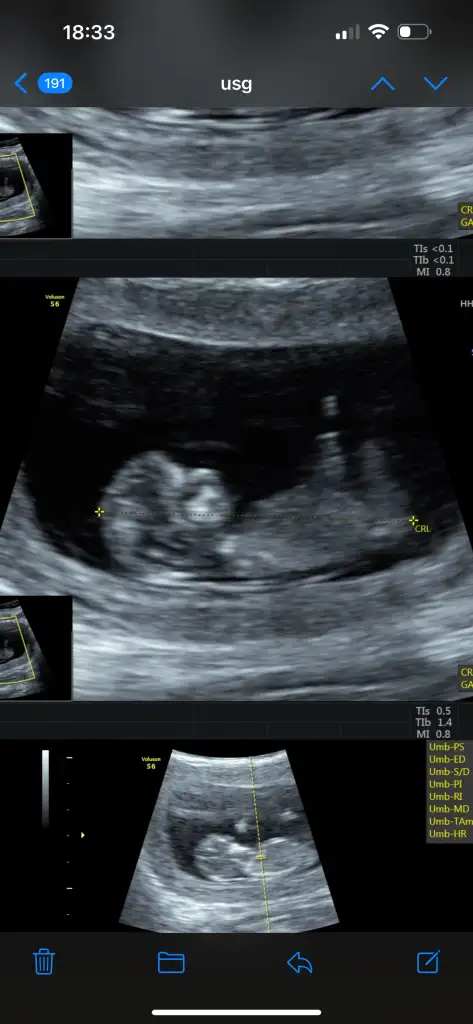

Benim 8 haftalık karından ultrasonu bu resim şuan 14 haftalığız haftaya öğrenirim sanırım yazarım buraya tahminini paylaşırsan sevinirim 🥰